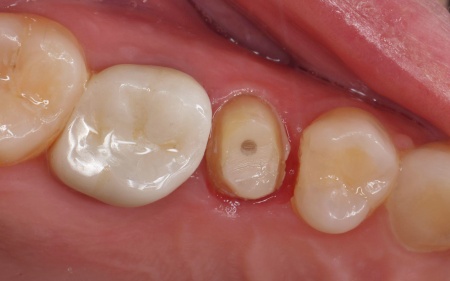

レントゲン撮影をして詳しく拝見したところ、右上奥歯の頭部分「歯冠」が縦に割れる「歯冠の垂直破折」が確認できました。

割れ目が深い場合は、歯の温存が困難です。

今回の症例では、症状や割れ方に応じて治療方針を慎重に判断する必要があると診断しました。

まず、割れている部分をしっかりと確認し、必要な部分を除去してから根管治療を行います。

薬剤を歯根の先までしっかりと詰め、支台築造で土台を作製したあと、被せ物を作製しました。